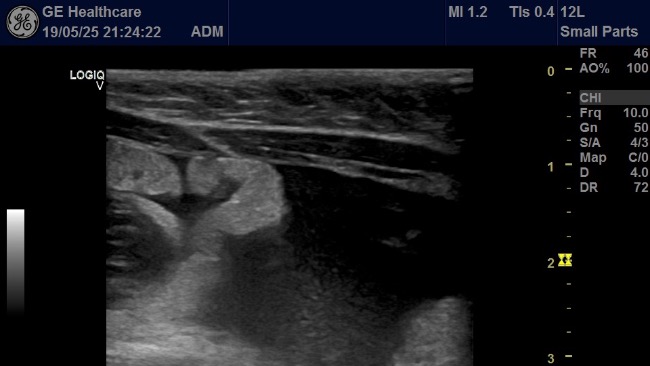

Migotka miała podwyższoną temperaturę, była apatyczna, przestała jeść. Badania krwi i USG potwierdziły najgorsze obawy: anemia, obniżone białko, płyn w jamie brzusznej. Wyniki są bardzo złe…leczenie trzeba było zacząć natychmiast.

Badania 23.05